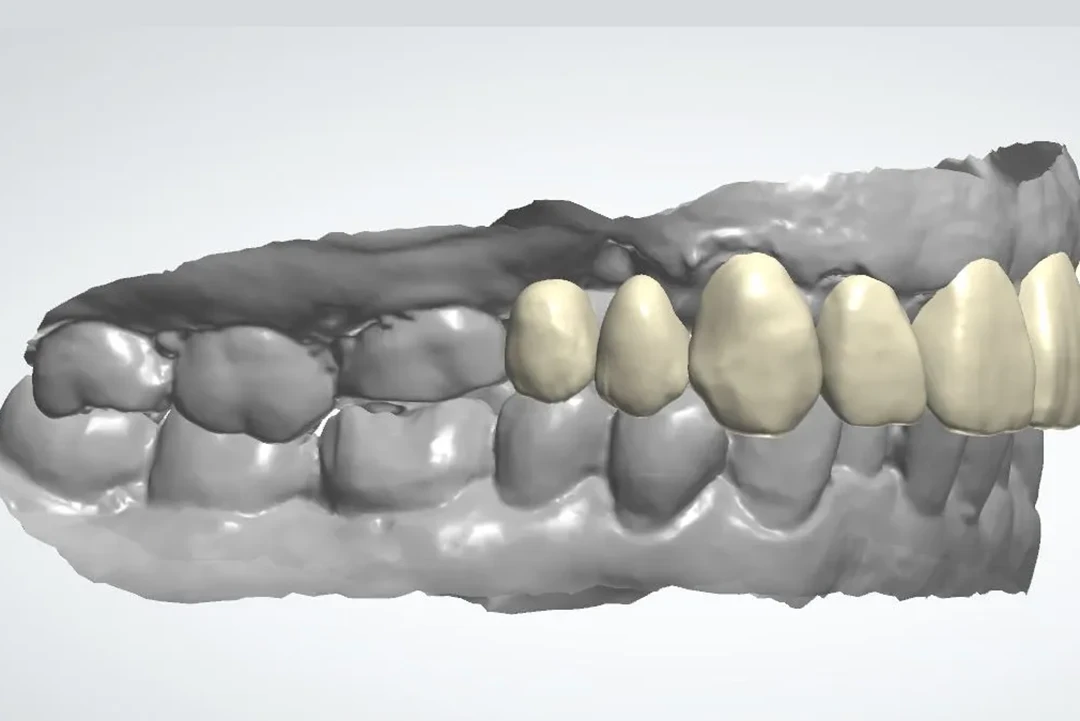

De 61 años nos visita con dientes dañados por caries y una prótesis antigua que ya no podía utilizar. Gracias a la planificación digital y la cirugía guiada, realizamos las extracciones y colocamos implantes con una prótesis fija el mismo día. Recuperó su sonrisa y la confianza de inmediato.